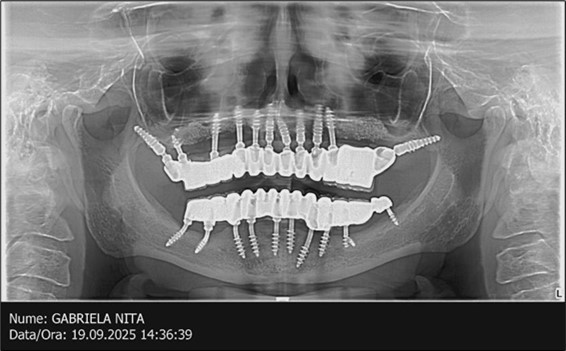

June 2022: Patient presented to our clinic for immediate-loading implant treatment At the time of presentation in 06. 2022, radiologically, advanced peri- implantitis is observed around the implants, with loss of native bone in the affected distal areas (Figure 1)

Figure 1.Panoramic overview picture before rehabilitation 06.2022

The results of rehabilitation treatment with corticobasal and compressive implants with a polished surface after the failure of two stage implants were highlighted over a period of 3 years and 3 months as being very good (Figure 14, Figure 15), with the patient completing a satisfaction survey in this regard. Certainly, it is necessary to continuemonitoring these results in the long term.